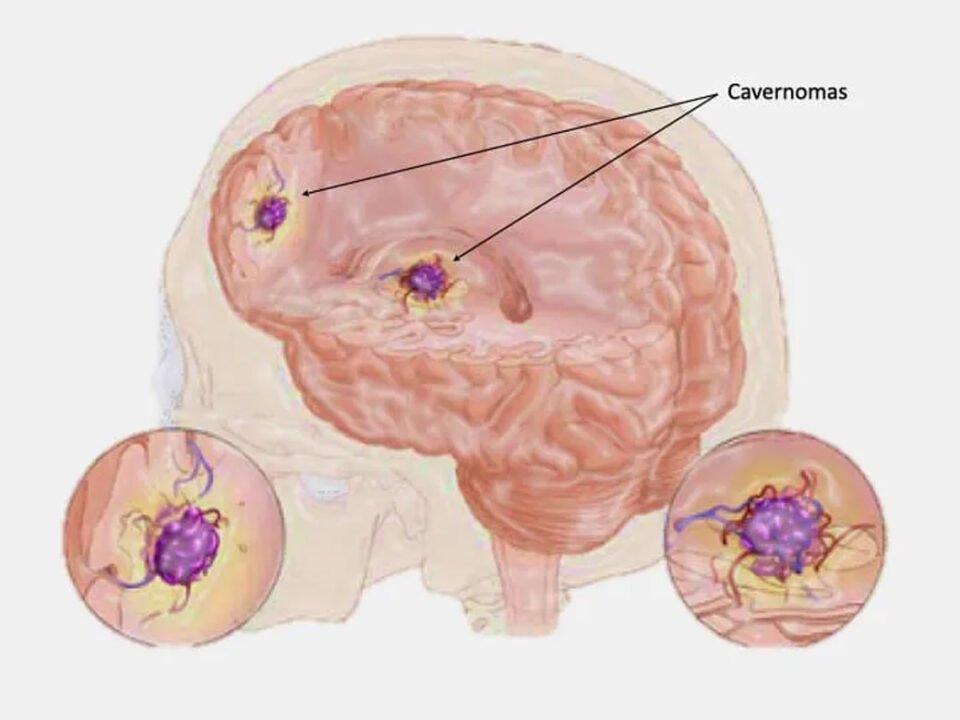

Cavernomas

O que é um cavernoma? Os cavernomas, também conhecidos como malformações cavernosas ou angiomas cavernosos, são lesões vasculares benignas formadas por aglomerados de capilares dilatados e […]